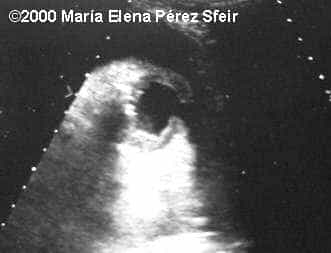

Cleft-lip, unilateral MarÃa Elena Pérez Sfeir, MD Article Published: May 30, 2002 Patagonia, Argentina This is an example of cleft-lip in a 3rd trimester fetus. Discussion Board Start a discussion about this article Add to Favorites Favorite